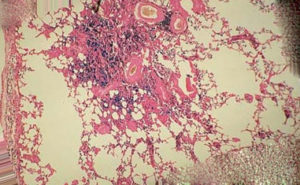

Гемосидероз